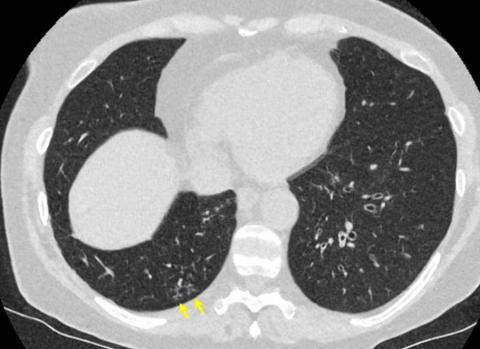

CO-RADS _____ (Equivocal - Features compatible with COVID-19, but also other diseases)

CO-RADS _____ (High - Suspicious for COVID-19)

CO-RADS _____ (RTPCR confirmed)

CO-RADS _____ (Low - Typical for other infections but not COVID-19)

CO-RADS _____ (very high level of suspicion for pulmonary involvement by COVID-19 based on typical CT findings)